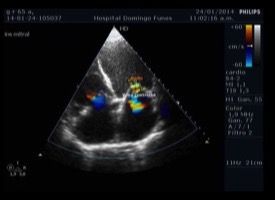

Sezioni Parasternali

Sezioni Apicali

Sezioni Sottocostali

Sezioni Sovrasternali